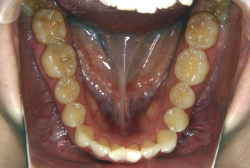

「歯並びの凸凹を直したい」という主訴で来院したケースです。診断の結果、たしかに「叢生」という隙間が足りないと言うことが原因の凸凹症例でした。

しかし、それ以上に問題なのは「前歯の噛み合い方が深すぎる」という症状で、初診の歯の正面写真を見ると下の前歯が全く見えません。こういう症状を矯正学では「過蓋咬合(かがいこうごう)」と言います。過蓋咬合を放置すると、将来的に顎関節に悪影響を与えるとされており、顎関節症の原因因子の一つです。また下の前歯の先端が、上の前歯の裏側の歯茎と強く接触するため、歯周病の原因にもなります。

検査の結果、凸凹が軽症なため非抜歯で矯正すること可能と判断、マルチブラケット装置にて治療しました。治療後は歯並びが綺麗になっただけでなく、噛み合わせ的にも正しい状態が確立しています。